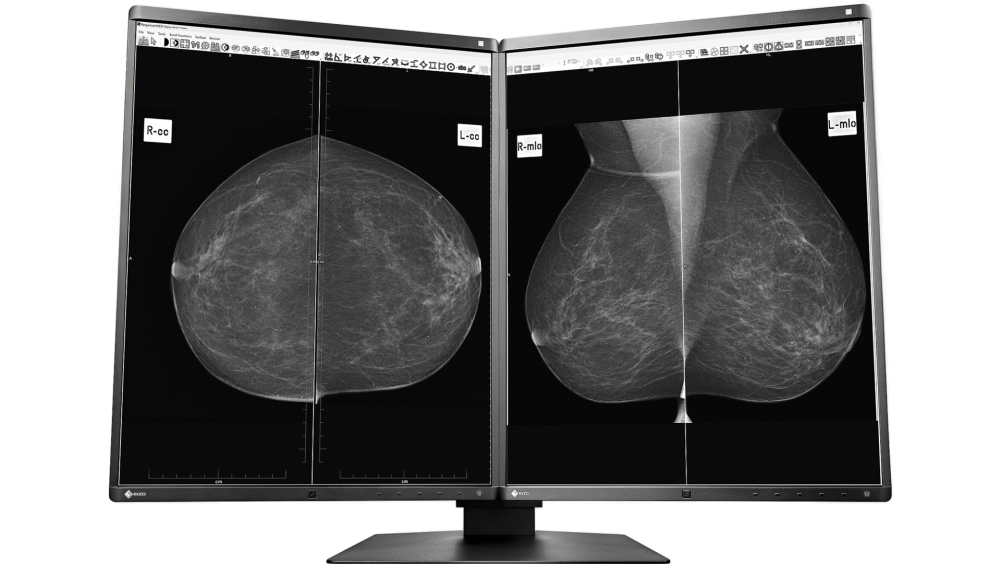

Digitale Mammographie

Digitale Mammographie Fujifilm Amulet S

Die Röntgendarstellung der weiblichen Brust (Mammographie) wird in unserer Praxis auf einem Festkörperdetektor (CCD) registriert und in digitaler Form an unser Bilddatennetz weitergegeben. Die digitale Speicherung der Bilder gewährleistet, dass auch nach Jahren noch Kopien oder Bildvergleiche in Originalqualität möglich sind. Die Auswertung erfolgt an einem hochauflösenden Multimonitor-System.

Monitor EIZO Radiforce GX560